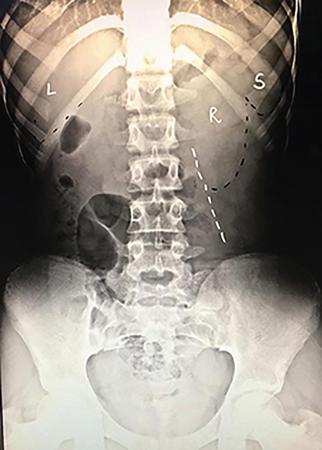

Various abdominal calcifications can be seen on the scout film and need to be differentiated from renal calcifications. They include gallbladder calculi which appear as multiple faceted calcifications in the right upper quadrant, calcific chronic pancreatitis which is seen as multiple stippled calcifications in the upper abdomen adjacent to the lumbar spine, adrenal or hepatic calcifications appear as stippled and discrete calcifications overlying the right twelfth rib. Renal calculus is seen as separate deposits of calcified density confined to the renal shadow. Other calcifications within the renal shadow include cortical and medullary nephrocalcinosis (Figs. 10.6.2 and 10.6.3). Stippled suprarenal calcification in a paediatric patient may point towards a neuroblastoma while rim calcification may be seen in a case of adrenal haemorrhage (Fig. 10.6.4). Calcifications seen in the pelvis can point towards a bladder calculus, ureteric calculus, phlebolith or an intrauterine copper device, calcified fibroid or dermoid cyst in a female patient.

Image

Fig. 10.6.2 Diffuse calcification of bilateral renal cortices suggestive of cortical nephrocalcinosis. It can be associated with chronic glomerulonephritis, shock, sepsis, chronic pyelonephritis etc.

Fig. 10.6.3 Deposition of calcium salts in the medulla of the kidney suggestive of medullary nephrocalcinosis. It can be associated with hyperparathyroidism, medullary sponge kidney, renal tubular acidosis (type 1), hypervitaminosis D, milk-alkali syndrome etc.